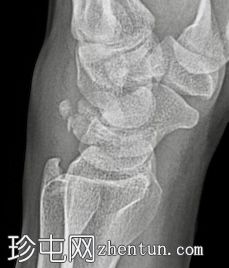

左腕关节正位和侧位X线片显示三角骨撕脱性骨折,仅在侧位片上可见,放大锐化后骨折线显示更清晰。